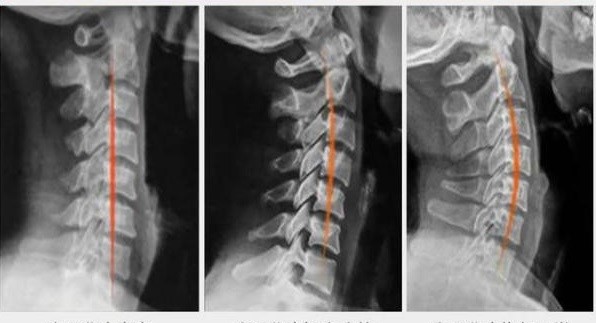

对于颈椎来说,最重要的一个东西叫做弧度,因为我们正常的颈椎是像下图最右侧一样的,而我们很多人去体检的时候可能经常听说过生理曲度变直这样的词语,所谓生理曲度变直就是像下图中中间和左边的一样。

为什么会出现那么多生理曲度变直的情况,最大的原因就是随着智能手机的出现,大家养成了经常低头的习惯,经常低头最大的危害会让颈椎承受更大的压力,有人曾经做过试验,当颈椎屈曲60度时,颈椎会承受将近四倍头部的重量,而这就是出现颈椎提前老化,椎间盘突出的重要原因。